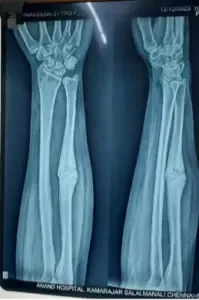

| Oct 2023 | Observation After 28 days x-ray showed evident callus formation. (Figure 2) Pain 90% reduced. Swelling 80% reduced Weakness persists. |

| Dec 2023 | Patient came for follow up X-ray showed complete callus formation. (Figure 3) |

Callous Formation

After Intervention